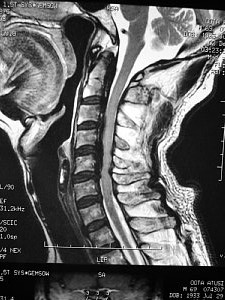

難病の頚椎後縦靱帯骨化症の手術前 |

手術後 | ||